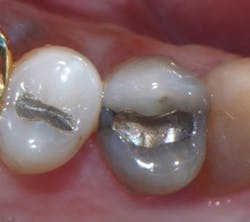

A 68-year-old patient presented with the upper right first premolar with occlusal amalgam and two distal marginal ridge fractures and discoloration under the mesial marginal ridge (figure 1). He previously had an extraction due to a fracture on his lower arch and wanted to treat the upper first premolar proactively. The existing occlusal amalgam was removed under rubber dam isolation. Caries were visualized clinically, and cracks were visualized with transillumination under both marginal ridges (figure 2). The premolar was prepared using a nonretentive cavity preparation design to allow the resin to flow in, out, and around the tooth (figure 3). Particle abrasion with 27 microns at 40 psi (PrepStart, Danville Products) was completed for microretention and biofilm removal before matrices, phosphoric acid etch (figure 4), and adhesive were placed.